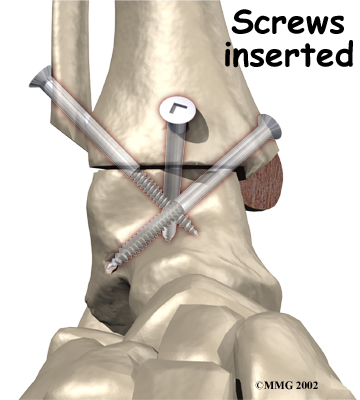

It is important when the surfaces are removed that the angles of the cut surfaces are correct. When the tibia is brought against the talus, the foot should be at a right angle to the lower leg. Once the cuts are made the bones must be held in place while they fuse. This can be done using large metal screws and metal plates if necessary. The screws are usually under the skin and are not removed unless they begin to rub and cause pain.

Inserting the screws